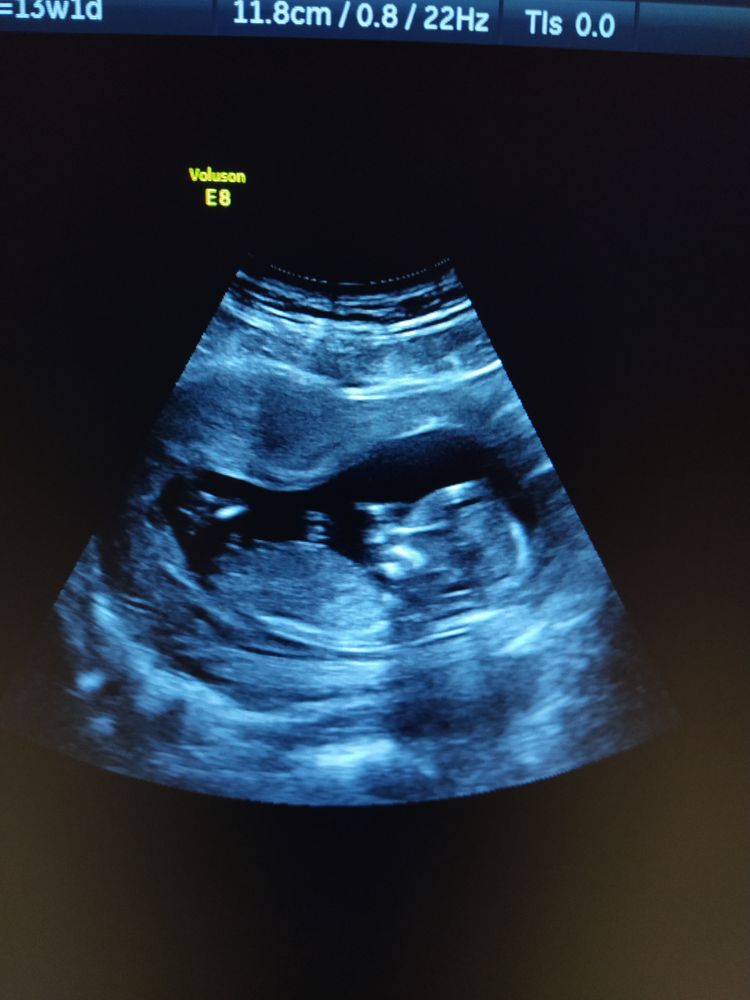

Мальчик или девочка.

Пол малышаСегодня была на первом скрининге. Слава Богу вроде все хорошо, теперь ждём результатов крови. Девочки, посмотрите мальчик или девчуля.

Я бы сказала мальчик

Если это половой бугорок, то он торчит как бы немного вверх, а не параллельно

Но это все вилами по воде, честно)

Только врач может предложить